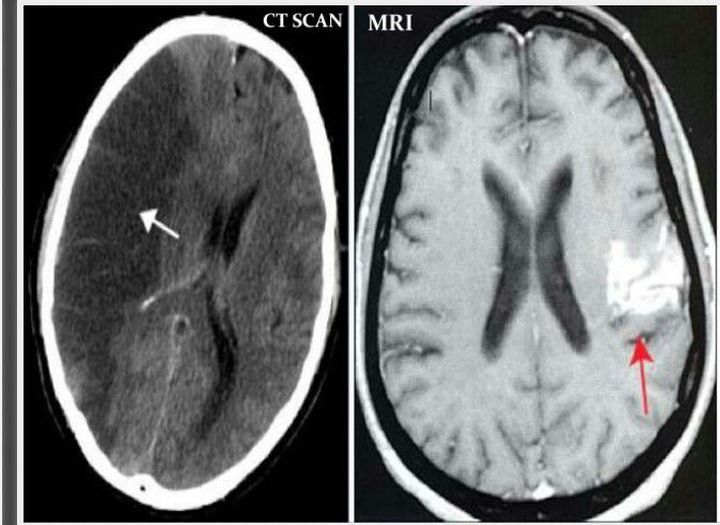

Ischemic stroke

Mri

Stroke

Ct Scan